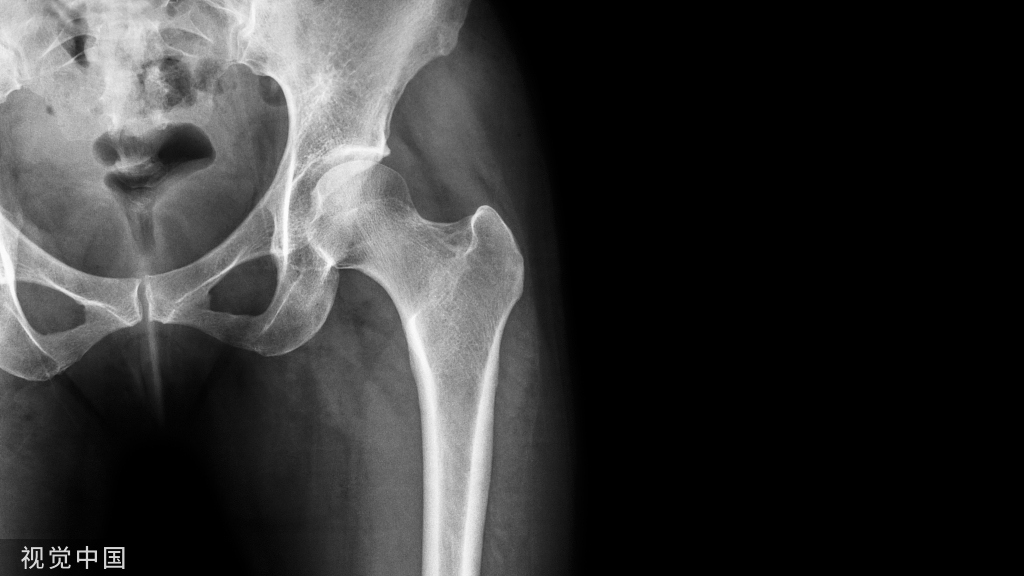

”骨水泥手术“  适合哪些人群

• 骨质疏松性椎体骨折患者疼痛缓解

• 不稳定骨质疏松性椎体压缩性骨折

• 疼痛性椎体骨折伴骨坏死(Kümmell病)

• 椎体血管瘤

• 骨髓瘤

• 椎体原发及转移性恶性肿瘤

• 部分椎体良性肿瘤